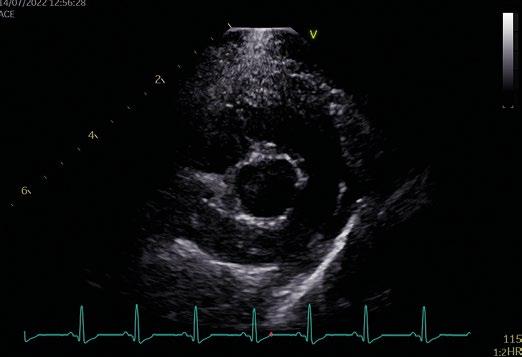

Utilidad clínica de la ecografía pulmonar y cardiaca en urgencias